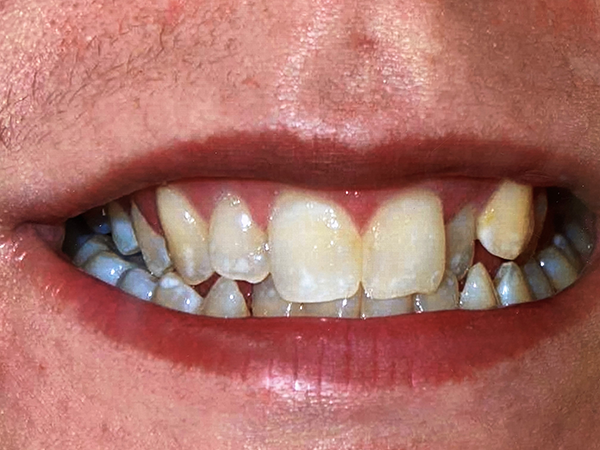

Micro Air Abrasion

Spots on front teeth

Spots removed